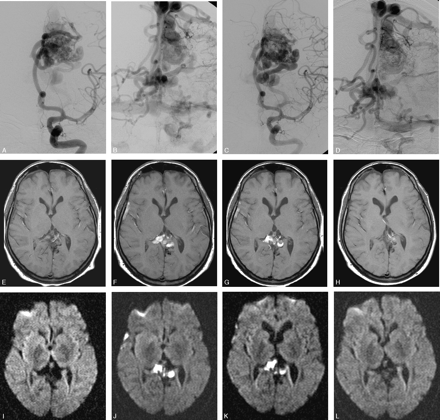

Parietal high-flow AVM with deep and bilateral cortical drainage.

A–D, Frontal left internal carotid angiogram, early and late phase, before and after the second embolization. Patent venous drainage is seen after the treatment.

E–L, Axial MR (E–H, T1-weighted, and I–L, DWI [b 1000]) immediately posttreatment, at 23 days, 35 days after treatment, and before a third treatment, 3 months later. The images illustrate the development of venous thrombosis 3 weeks after treatment in the deep and contralateral cortical veins with a complete resolution at follow-up.

M–U, rCBF (M–O) and rCBV (P–R) with the corresponding MTT (S–U): unchanged PI images after treatment (left column) are followed by a dramatic increase in MTT (severe drop in rCBF with a mild rCBV increase) 3 weeks later (middle column). A slow but almost total normalization of PI pattern was seen 9 days later (ie, after hypervolemic hemodilution) (right column). The patient was left with no symptoms.